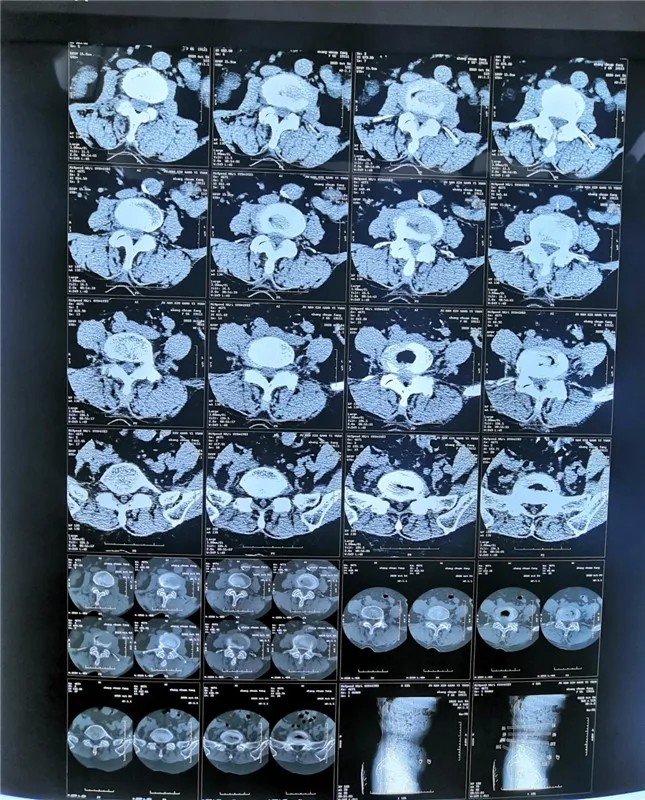

患 者:男,58岁。

主 诉:右下肢放射性疼痛1个月,加重5天。

现病史:患者慢性腰腿痛病史10年,间断发作,多次在当地医院行保守治疗,近1个月疼痛加重,以右下肢放射痛为主,右小腿前外侧为重,不能行走,影响睡眠。

查 体:双侧直腿抬高试验阴性,右小腿前外侧、右足拇指背侧感觉减退,右足拇指背伸肌力3级,右下肢股四头肌肌力4级,左下肢肌力5级。VAS评分9分

影像资料:

诊 断:

腰椎管狭窄症;腰椎间盘突出症;老年退变性侧弯。